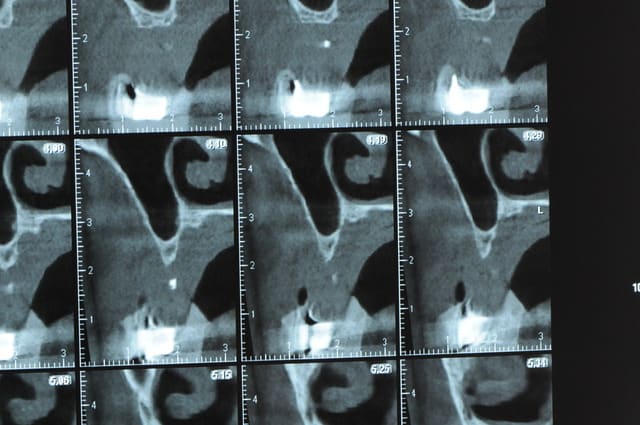

Une petite étude de ton cas D57

Sous réserves bien sur de voir l’animal en vrai

Les zones exploitables radiologiquement parlant:

Coupes implant

2,3 40100

4,96 35130 avec sinus lift mais difficile

5,25 35150

6,02 35130

6,78 35115 après réduction de hauteur de crête

7,26 35115 après réduction de hauteur de crête

8,51 35150

10,43 40115 ou 50115

11,10 40115

Ce qui nous fait 9 implants possible évidement avec un comblement de sinus on augmenterait encore les zones implantable mais ce n’est pas le but recherché, avec 8 (4+4) il doit être possible de faire une belle barre support de complet

Je n’ai pas eu le temps de te téléphoner, ça viendra